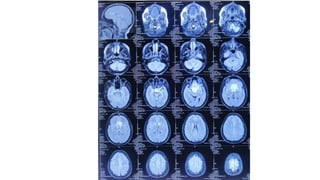

Radiological findings • Multiplanersagital ,coronal and axial images show a well defined ,midline, broad dural based, lobulated T1WI iso , T2WI iso to slightly hyper and FlAIR hyperintense mass noted in suprasellar area having extension forwards along the planum sphenoidale and backwards along the dorsum sellae. • After IV contrast avidly homogenous enhancement of the lesion and adjacent linear dural enhancement over the clivus and planum sphenoidale representing dural tail are noted. • The lesion causing compression over the optic chiasma, pituitary gland and floor of 3rd ventricle, and encasing the supraclinoid ICA, ACA and MCA of both sides. • The mass effect is evidenced by obliteration of Suprasellar & interpeduncular cysterns and symmetrical indentation of underlying cerebral cortex. • No perilsional edema is noted • However lateral , 3rd and 4rth ventricles appear normal • Complementary CT cut was taken and showing iso to slightly hyperdense lesion. No calcification is noted. Bone CT shows bony hyperostosis at planum sphenoidale .Sellar size is within normal limit

Radiological diagnosis • Suprasellarmeningioma with planum sphenonale and dorsum sallar extension

MRI

• T1WI

Typically iso-to slightly hypointense with cortex

Necrosis, cyst, hemorrhage(8-23%)

Look for gray matter buckling

• T2WI

Frequently isointense

Best sequence for visualizing CSF/vascular cleft between tumour and

brain

identifying vascular flow void(80%)

• FLAIR

Hyperintense peritumoral vasogenic oedema

Vasogenic oedema does not correlate with tumour size

• T1WI C+(best imaging tool)

>95% enhance homogenously ,intensely

Dural tail sign(35-80% of cases) non specific

A linear contrast –enhancing “dural tail” extending from the tumour

along the dura matter

En plaque: sessile thickened enhancing dura